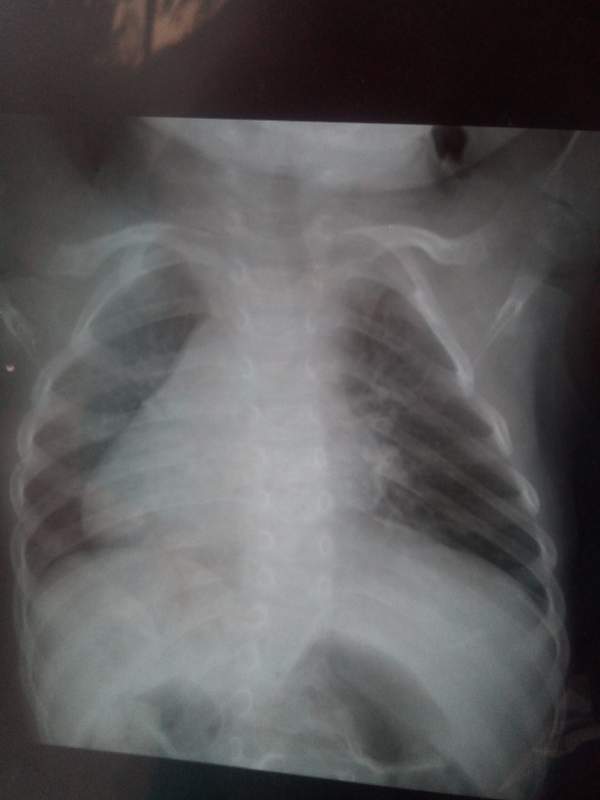

ÃÃÃÃÒòÖÎÁÆÑÓÎó£¬ÏÖ²¡Çé¼ÓÖØ£¬ÃæÁÙ̱»¾£»Õ÷Çó¸÷λ³æÓÑÌá³ö±¦¹óµÄÒâ¼û£¬½«¸Ð¼¤²»¾¡